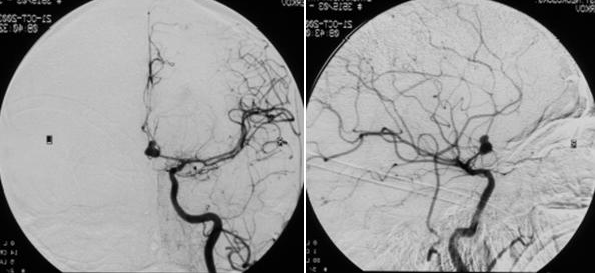

Через 24 часа после поступления при ангиографии была выявлена аневризма ПМА-ПСА справа (Рис. №1) и произведена операция: треппинг-клипирование аневризмы ПМА-ПСА справа (выключена шейка аневризмы вместе с ПСА), с частичным удаление внутримозговой гематомы правой лобной доли и удалением костного лоскута с пластикой твердой мозговой оболочки с целью наружной декомпрессии.

Во время операции визуально и допплерографически выявлялся выраженный спазм обеих ПМА. Были визуализированы сгустки крови, грубые спайки вокруг сосудов основания мозга и в хиазмальной области. На этапе выделения аневризмы произошел ее разрыв. Аневризма была выключена вместе с ПСА (поскольку шейка аневризмы была широкой и включала в себя эктазированную ПСА) на фоне временного клипирования обоих А1-сегментов ПМА в течение 20 минут. Кровопотеря составила около 500 мл, была адекватно восполнена интраоперационно.